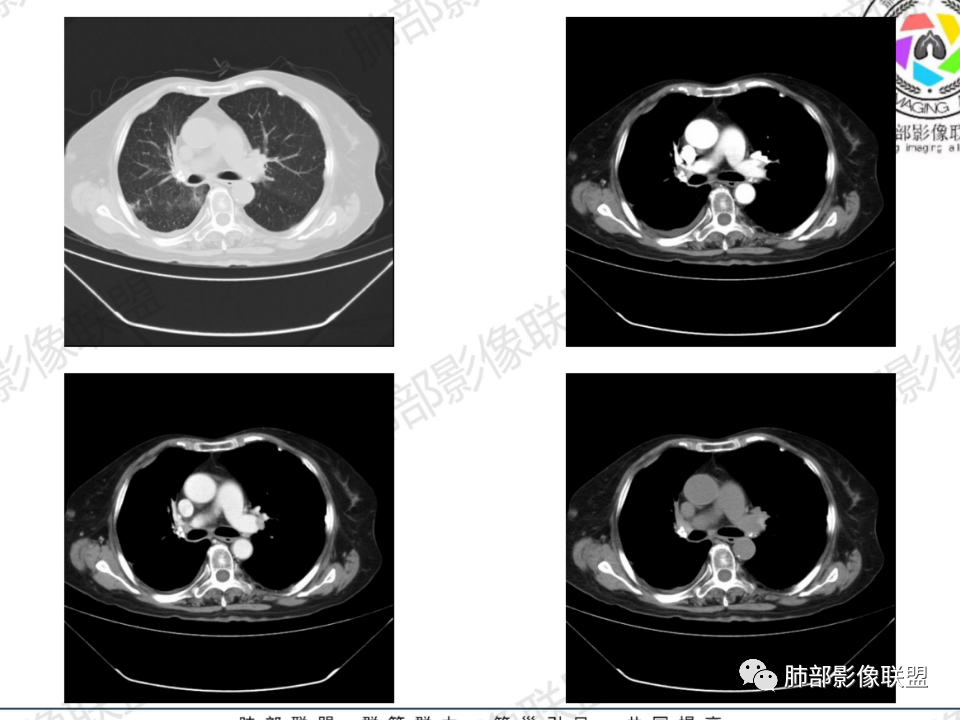

临床信息:老年女性,亚急性病程,咳嗽发热。有激素使用史。既往有淋巴结结核病史。肿瘤标记物Ca125升高。血沉升高,C反应蛋白轻度异常。 影像所见:右侧胸廓相对狭小,右肺上叶不规则团块影贴附纵隔旁,轻度分叶,整体密度较均匀,偶见钙点。

相应上叶尖端及前段支气管开口未能追踪(阻塞),开口处见钙化。病灶渐进性强化,并衬托出较完整尖段及前段含液支气管影。支气管开口区域未见异常高密度强化(如类癌等)及相对乏血供区(如鳞癌)。病灶区未见液化坏死。右上纵隔及胸廓入口区未见病灶胸膜外突破(栽赃)。

右肺上叶后段等区域散在片状影,边界不清(提示渗出性病灶)。

纵隔及双肺门见钙化淋巴结。心包积液,右侧胸腔积液(提示存在活动新病灶)。双侧胸膜下见多发斑点状钙化,胸廓变形(提示存在结核基础病变可能)。 诊断意见:综上,右肺上叶块状影更符合继发性肺结核。 最后小结:既往诊断淋巴结结核,提示已治愈。近2年服用激素,可疑诱导结核复燃,也可引起发热。纵隔肺门淋巴结肿大钙化,压迫支气管,右肺上中下叶支气管均狭窄,所以引起喘息咳嗽。尖段支气管受累闭塞,导致肺不张、支气管粘液栓,出现条状无强化区。病变累及胸膜,导致结核性胸膜炎并胸水,引起右侧胸痛。实验室检查血沉快,CA125高,低蛋白,均符合结核。下一步,建议支气管镜尖段支气管刷检并抗酸染色。(本段摘自於雄老师精彩发言)